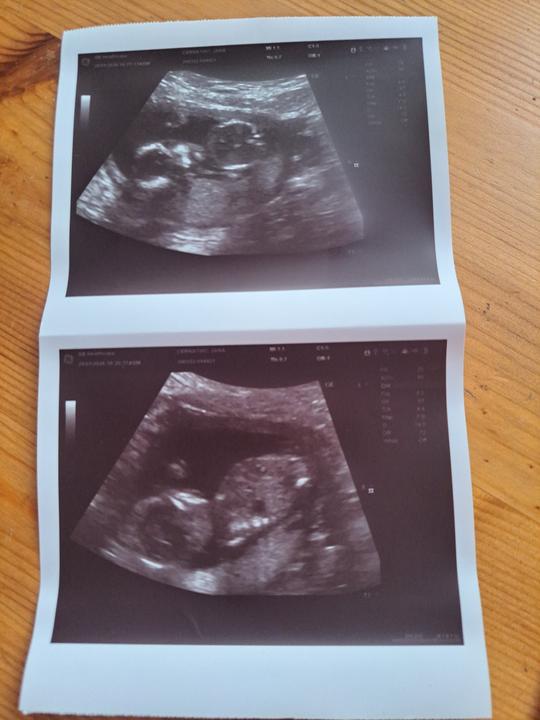

Naše krásná bublinka 🥰💞❤️🍀🍀🍀🍀